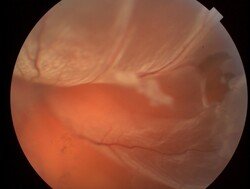

Imágenes

Figura 4. Desprendimiento de retina casi total con desgarro supero temporal y su imagen luego de vitrectomía con láser y gas C3F8 al 15%.